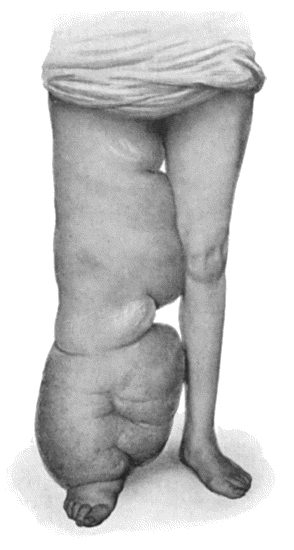

89.Elephantiasis Neuromatosa in a woman æt. 28 359